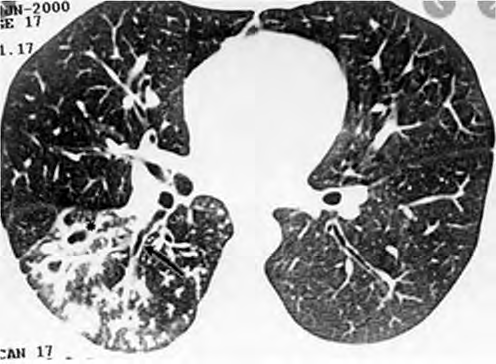

Um adolescente de 17 anos de idade procura atendimento em função de tosse vespertina, febre e hemoptise em pequena quantidade. Refere sudorese noturna e perda de peso. A tomografia de tórax apresenta nódulos centrolobulares com padrão de árvore em brotamento, além de pequenas cavitações espessas e de paredes irregulares, bem como brônquios espessados em segmento posterior do lobo inferior direito, conforme a imagem a seguir.

Acervo Pessoal.